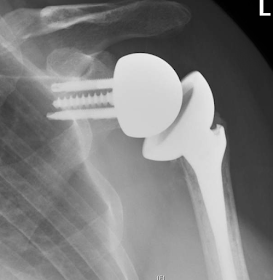

Unless the tuberosity can be mobilized and fixed securely, a primary reverse total shoulder might have been a consideration at the index surgery, as shown in the x-ray below of a reverse total shoulder (also with an 'absent tuberosity sign').

Note that, in contrast to our usual impaction grafting approach, this stem needed cement for control of prosthetic height and version.